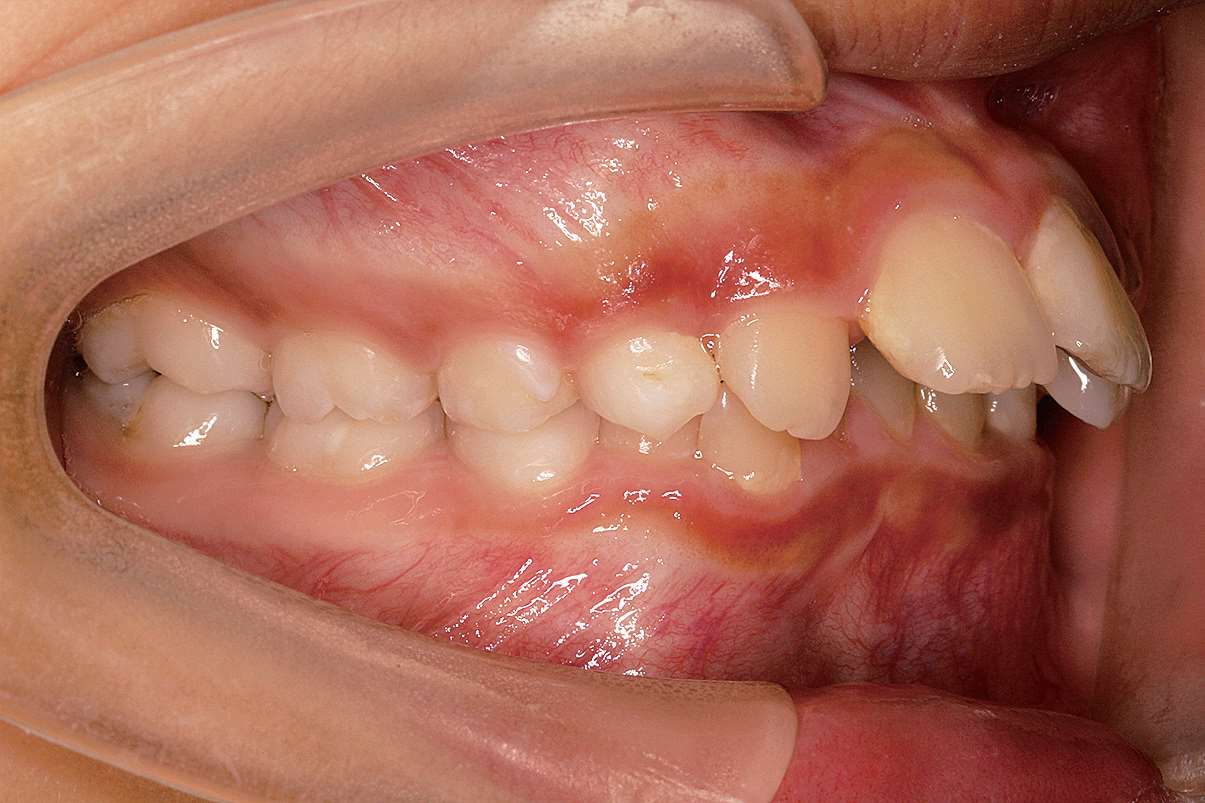

图 2-5 Ⅱ类 1 分类口内照片

图 2-6 Ⅱ类 1 分类错

的特点

A.正常

;B.上颌牙唇倾;C.上颌前突;D.上、下颌后缩,上、下前牙唇倾;E.上、下颌后缩,上颌前牙唇倾;F.上颌前突,上、下前牙唇倾;G.下颌后缩(摘自Eustáquio A. Araújo and Peter H. Buschang

[1]

)